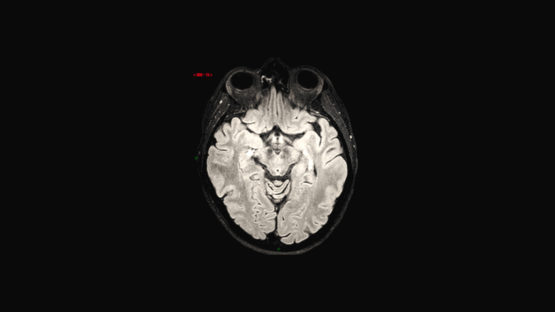

In medical research, seeing really is believing. Imagery is increasingly at the very heart of what researchers do. Doctors can now see more, see earlier and therefore treat conditions more precisely. They can also more precisely monitor the effectiveness of the medicine they prescribe. The result is simple: more lives are saved.

How do you make a machine attractive? How can you make as many people as possible understand that this machine could save lives? Once again, we decided to tell stories. Those of patients but also those of doctors. Men and women who are ill and – thanks to research – whose vital prognosis was positive. The MRI plays a fundamental role in the research. This is what the researchers and those with the illness talk about, with feeling. We also used a series of visual metaphors to convey emotions which are often a driving force in sponsorship.

From a technical point of view, we faced a challenge. Filming inside a working MRI lab is totally impossible. So we recreated this one using real images and 3D simulations.